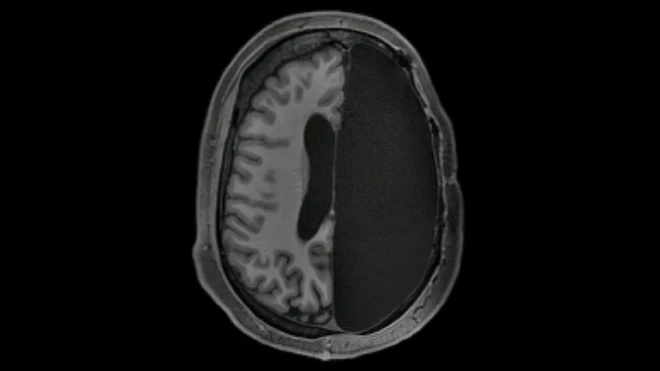

ที่มาของภาพ, UNIVERSITY OF OXFORD

รายงานวิจัยที่ตีพิมพ์ในวารสาร Nature Communications ระบุว่า มีการวิเคราะห์ผลสแกน MRI จากสมองของกลุ่มตัวอย่าง 22,000 ราย ที่มีอายุระหว่าง 40-70 ปี ซึ่งผลสแกนนี้ได้จากคลังข้อมูลชีวภาพ UK Biobank

จากนั้นทีมผู้วิจัยได้พิจารณาผลสแกนสมอง โดยดูว่ามีความเปลี่ยนแปลงของ pathway หรือวิถีการเชื่อมต่อของเนื้อสีขาว (white matter)ในสมองส่วนต่าง ๆ อย่างไรบ้าง ทั้งเปรียบเทียบความเปลี่ยนแปลงเชิงโครงสร้างนี้กับข้อมูลสุขภาพ และความสามารถในการคิดของกลุ่มตัวอย่างแต่ละคนด้วย

ผลปรากฏว่ากลุ่มตัวอย่างที่มีปัจจัยเสี่ยงต่อโรคหลอดเลือดสมองสูง ซึ่งส่วนใหญ่ก็คือผู้ที่มีความดันโลหิตสูง เกิดการเปลี่ยนแปลงของวิถีเชื่อมต่อระหว่างเนื้อสมองสีขาวไปอย่างมาก แม้จะยังอยู่ในวัยเพียงสี่สิบกว่าปีเท่านั้น โดยดร. มิเชล เวลด์สแมน ผู้นำทีมวิจัยจากมหาวิทยาลัยอ็อกซ์ฟอร์ดของสหราชอาณาจักรบอกว่า

"ปริมาตรของเนื้อสมองส่วนหน้าและส่วนข้างที่ทำงานเป็นเครือข่ายเดียวกันลดลง และวิถีเชื่อมต่อของเนื้อสีขาวไม่สมบูรณ์เหมือนเดิม เนื่องความดันโลหิตสูงทำให้การไหลเวียนของเลือดไปเลี้ยงสมองผิดปกติ"